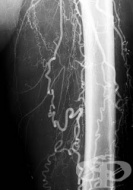

I77.3 Артериална фибромускулна дисплазия

Заболявания

Артериална фибромускулна дисплазия е състояние, което води до стесняване (стеноза) и разширяване (ан...